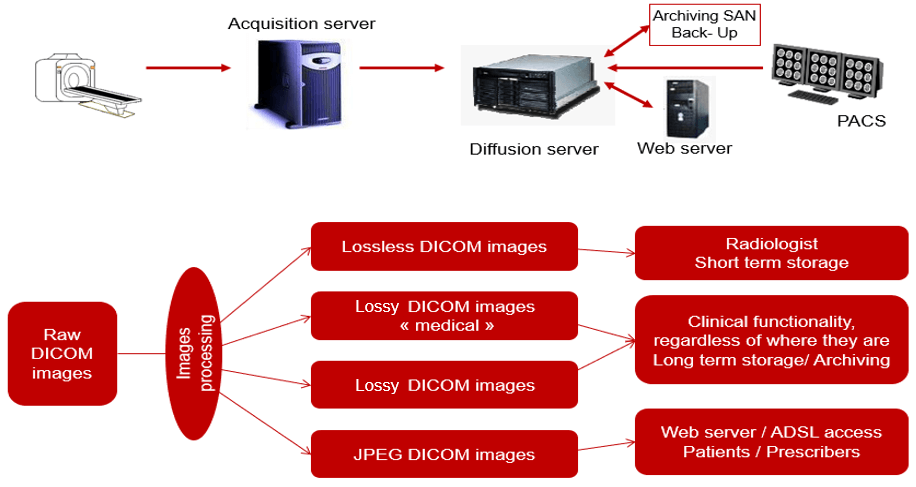

This simplified diagram indicates the image data flow between the imaging modality and PACS.

Acquisition

This simplified diagram indicates the image data flow between the imaging modality and PACS.

- Flow: Modalities -> PACS

The flow of “raw” format images. Acquisition protocol for each modality (automation and technologist dependent).

DICOM

DICOM is the international standard used to transmit, store, retrieve, print, process, and display medical imaging information. It involves the integration of image-acquisition devices, PACS, workstations, VNAs and printers from different manufacturers. DICOM is an acronym for Digital Imaging and Communications in Medicine and originated in 1983. It was developed and is maintained to meet the evolving technologies and needs of medical imaging today. It is free to download and use by institutions.